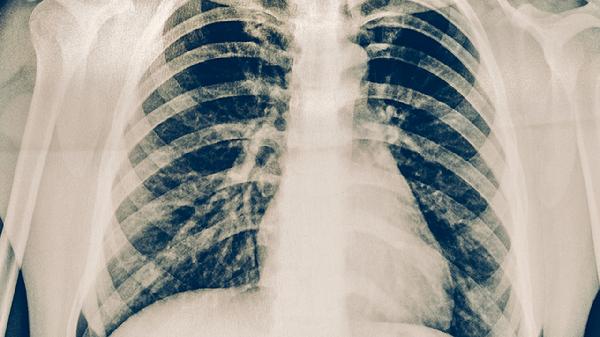

肺癌胸腔積液可通過胸腔穿刺引流、胸腔閉式引流、藥物治療、放射治療、手術(shù)治療等方式緩解。肺癌胸腔積液通常由腫瘤侵犯胸膜、淋巴回流受阻、低蛋白血癥、感染、心力衰竭等原因引起。

胸腔穿刺引流是快速緩解呼吸困難的有效方法,通過局部麻醉后在超聲引導(dǎo)下將穿刺針插入胸腔,抽出積液。該方法適用于中到大量積液且癥狀明顯的患者,操作后需監(jiān)測(cè)生命體征,防止氣胸或出血。積液送檢可幫助判斷性質(zhì),如發(fā)現(xiàn)腫瘤細(xì)胞可明確診斷。